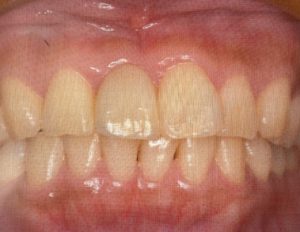

後は歯茎からの貫通部が細いためにインプラント周囲炎になりにくく、歯茎も下がりにくいという特徴があります。